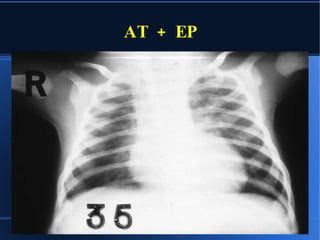

RX CON/SIN CARDIOMEGALIA OLIGOHEMIA CONGESTION CRECIMIENTO AD CRECIMIENTO VI AP CONCAVA

AT + EP